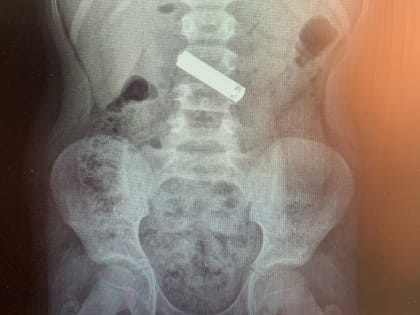

«Мизинчиковую» батарейку проглотил 9-летний мальчик в Воронеже

Фото: Воронежская областная детская клиническая больница №2 В Воронеже в областную детскую клиническую больницу №2 по скорой помощи доставили 9-летнего мальчика, проглотившего батарейку, сообщили в пятницу, 19 июля,